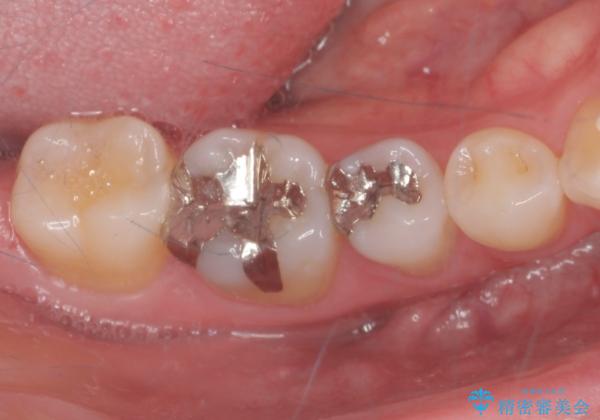

- 銀が目立つのがやだとの事で来院。

二つとも一緒に治療可能だが、まずは一箇所とのご希望だったので

一つずつ治療を行うことにしました。

銀の詰め物を外し、拡大鏡で虫歯がないか確認してe-maxインレーで治療をしました。